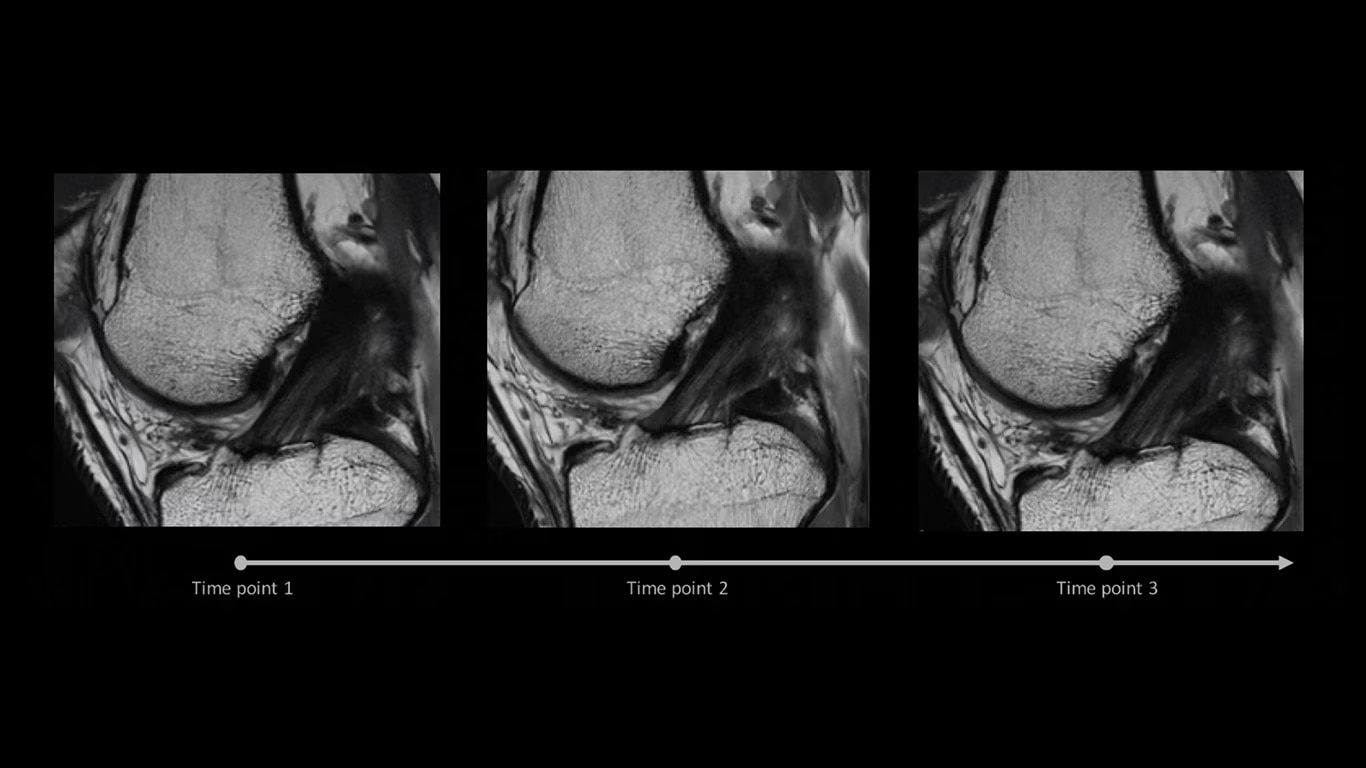

AIR x automatically detects patient anatomy and prescribes MRI slices for routine and challenging neurological and knee exams, delivering consistent and quantifiable results.

air-x-automated-mri-slice-ci-en

Deliver consistent MRI slice placements across multiple clinical time points, with a deep-learning algorithm that provides efficiency and time savings.

air-x-consistent-accurate-ci-en